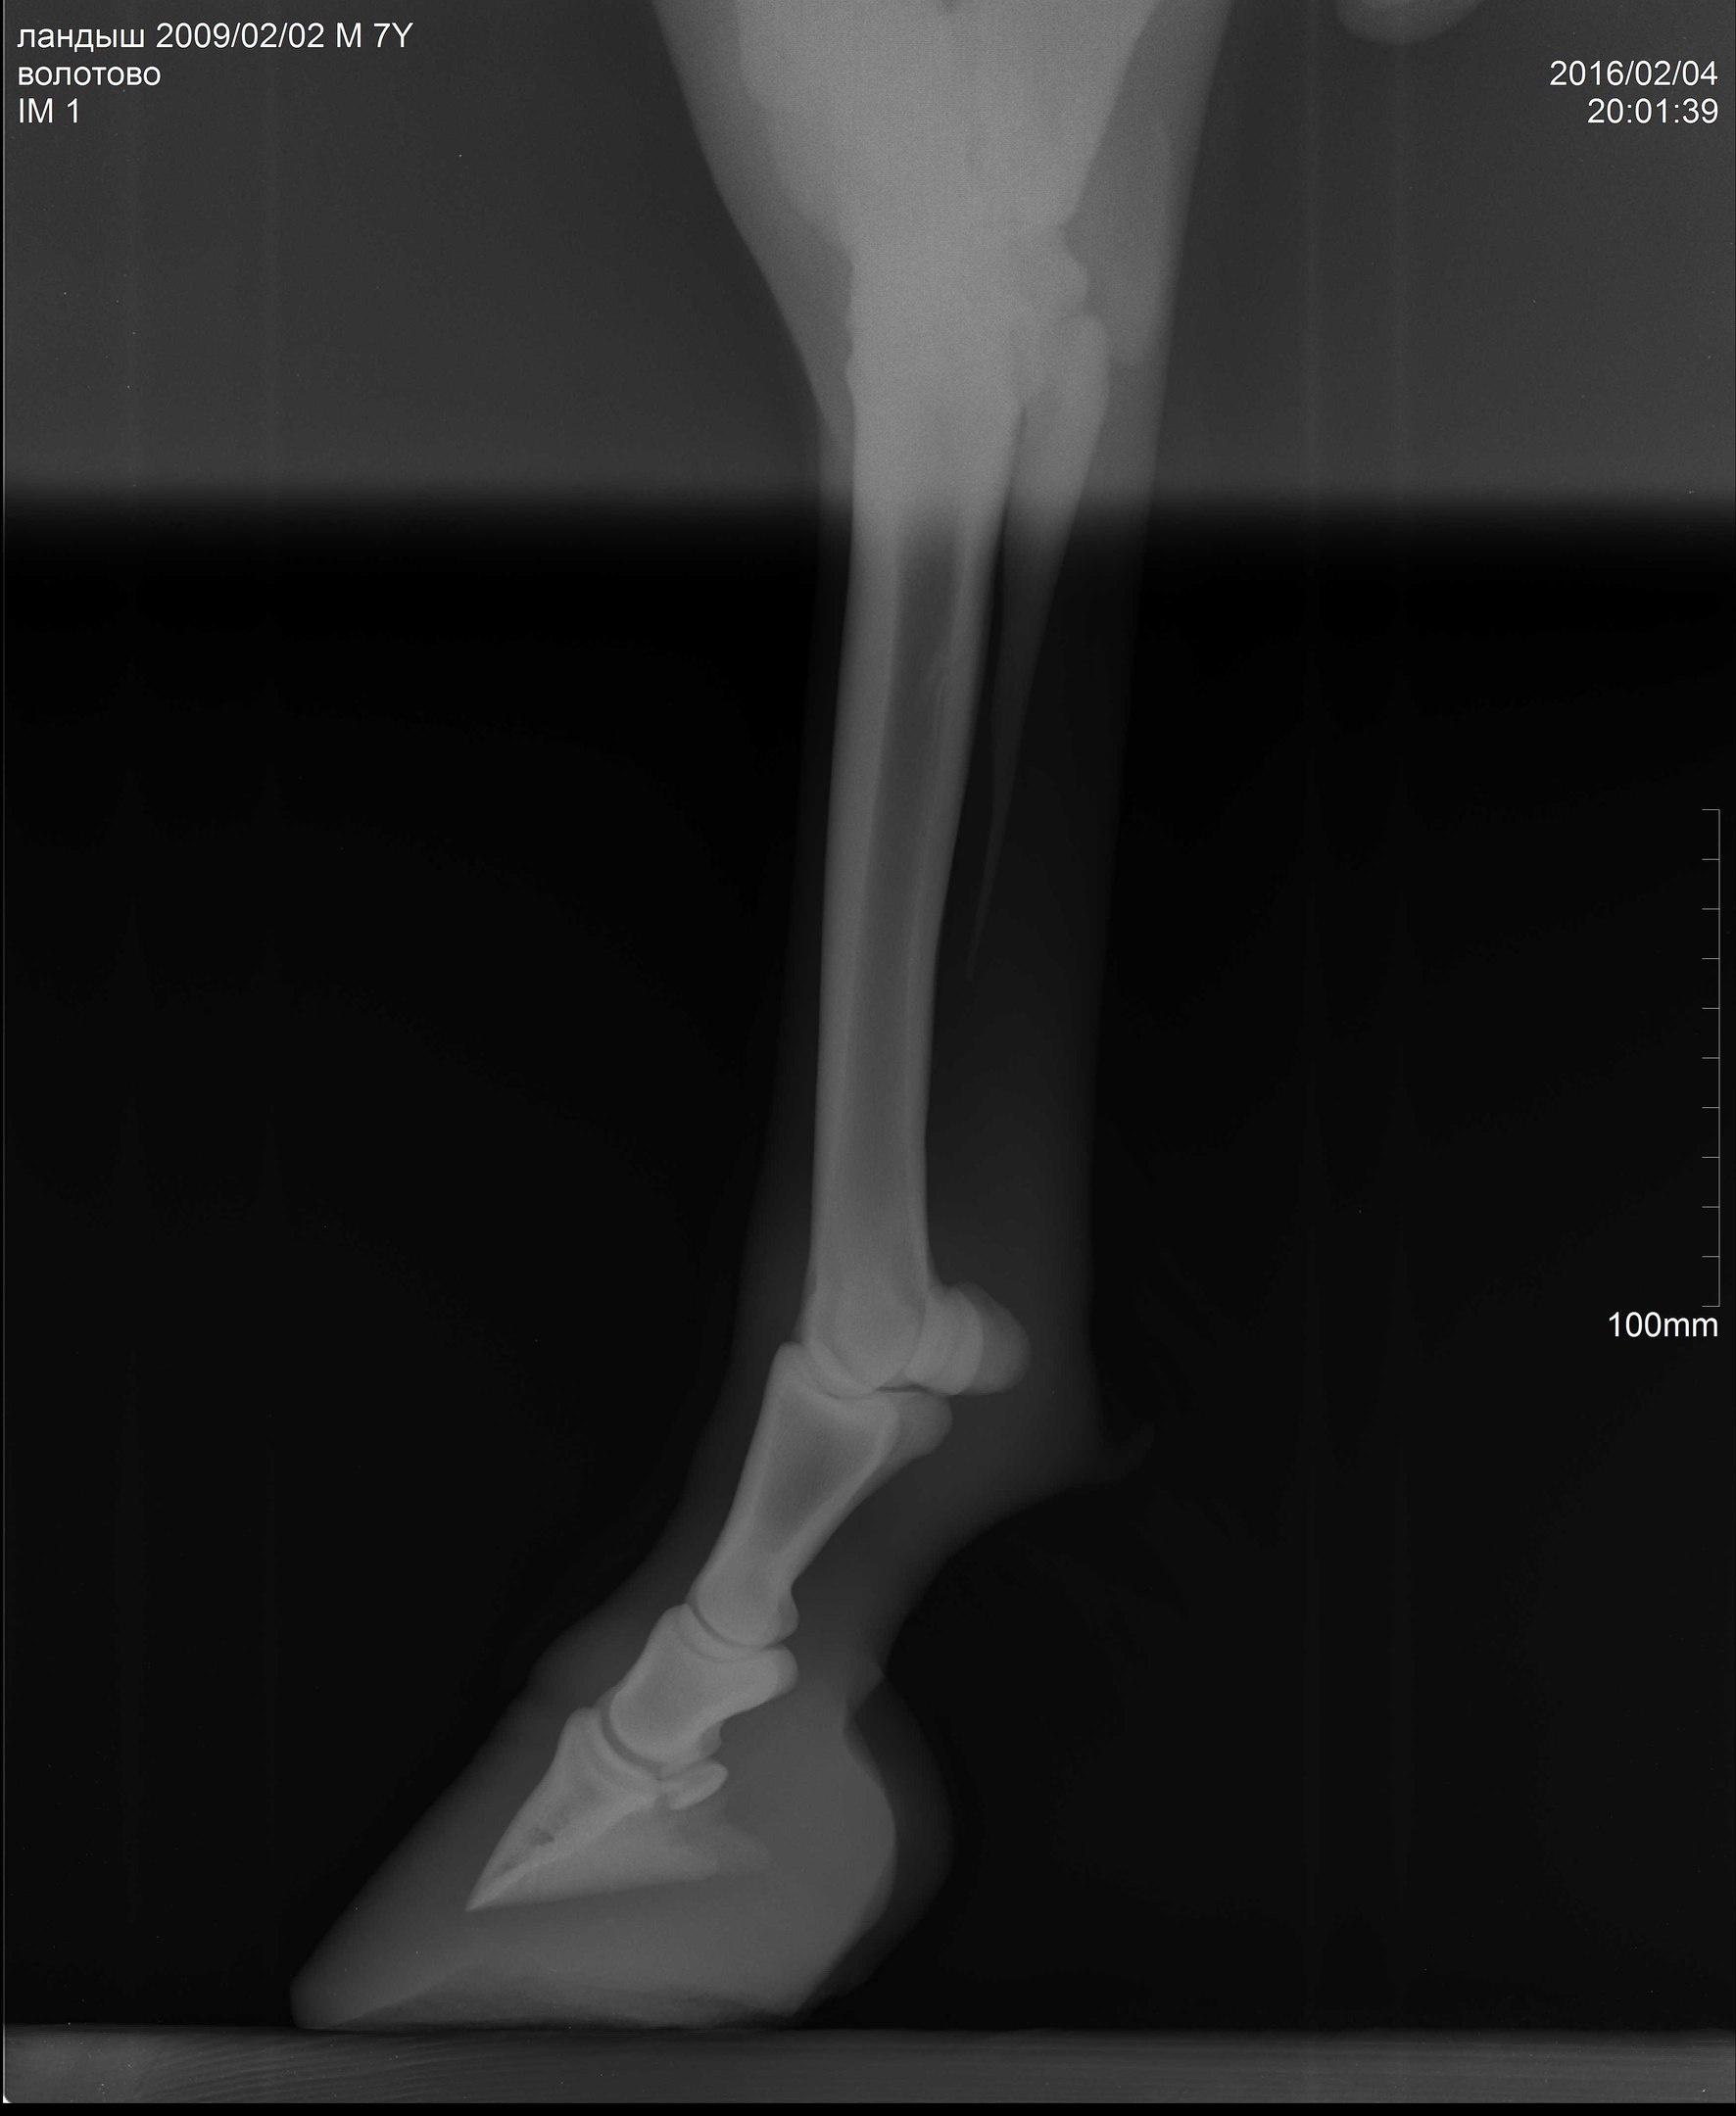

В общем, после чудесного-расчудесного лекарства Флуниджекта и замечательных обнадеживающих рентгенов пони всего лишь требовалась грамотная расчистка. Нужно было чуть изменить угол копыт, чтобы выправить копытную кость более-менее параллельно подошве (хоть в некоторых статьях я читала, что совсем необязательно эта параллельность должна быть нормой).

А тут нужна была тонкая, филигранная работа. Рентгенолог Анна мне оставила диск с программой, где можно было выверять углы, каждый миллиметр контролировать!!!! А я, конечно, со своими клещами и целью тупо на 1см понизить пятки, натворила дел (((